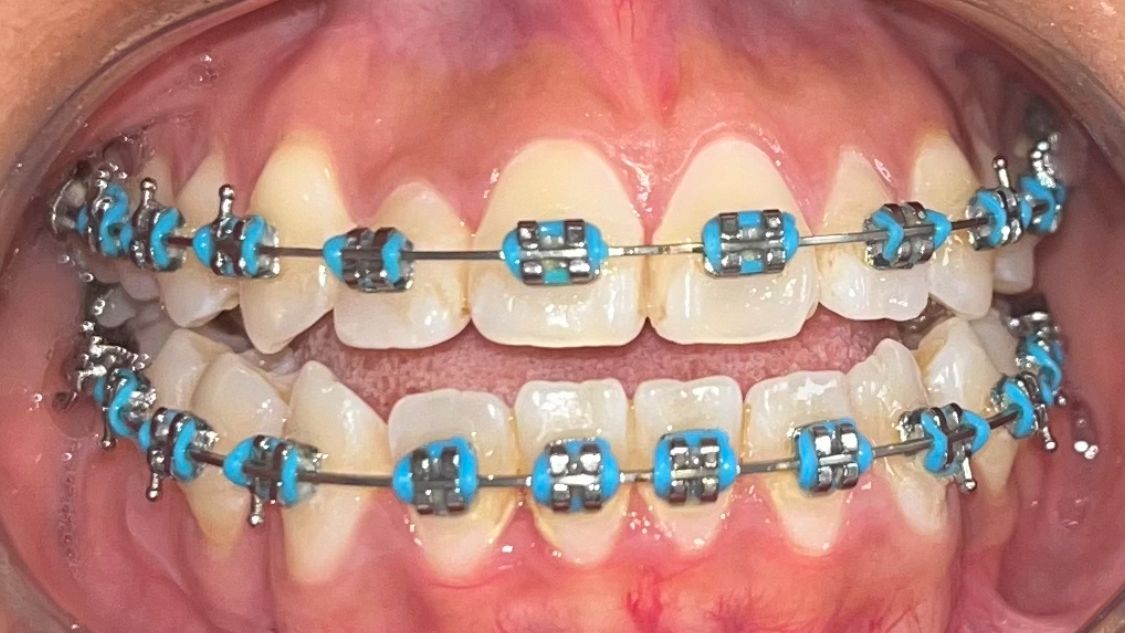

After

Before